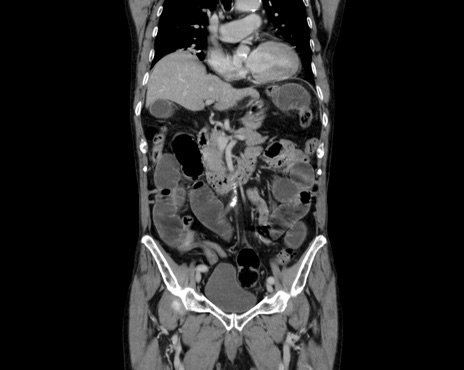

症例26(冠状断像)

【症例】80歳代男性

【主訴】嘔吐

【現病歴】昨晩2回嘔吐あり、今朝になっても嘔吐あり。来院。

【既往歴】胃潰瘍

【身体所見】意識清明、BT 37.6℃、BP 166/95mmHg、HR 100bpm、SpO2 97%、腹部:平坦・軟、腸蠕動音聴取良好、圧痛なし。

【データ】WBC 21900、CRP 1.4